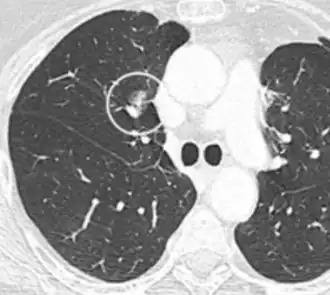

- A lung nodule abutting a pulmonary cyst is a rare finding, yet indicating cancer.[9]

- Bubble-like lucencies in the nodule indicate cancer:[9]

.png)

- Vascular convergence is where vessels converge to a nodule without adjoining or contacting the edge of the nodule, and is mainly seen in peripheral subsolid lung cancers.[9] It reflects angiogenesis.[9]